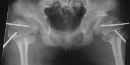

SPONDYLO-EPI-METAPHYSEAL DYSPLASIA WITH JOINT LAXITY (SEMDJL)

Radiographic features: